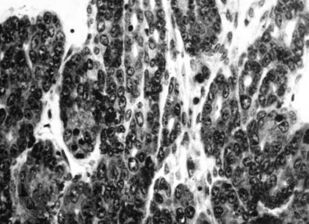

Книга посвящена описанию животных моделей in vivo для отбора, углубленного и/или доклинического изучения цитостатиков, а также некоторых таргетных средств. Представлены основные биологические характеристики, дополненные лекарственной чувствительностью и востребованностью в настоящее время.

Информационный материал предназначен для исследователей, работа которых связана с поиском, углубленным или доклиническим изучением in vivo новых противоопухолевых агентов.